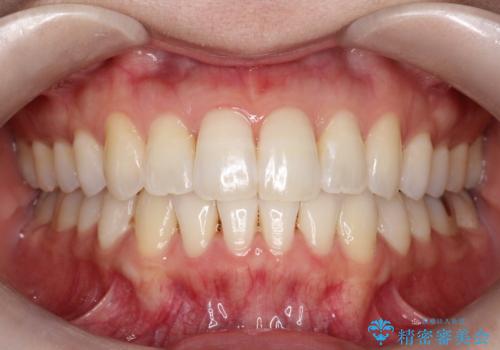

【インビザライン】前歯のガタガタを治したい

上の歯の前突も気になってたため、奥歯の遠心移動も行いながらインビザラインにて治療を行いました。

前歯も下がり満足していただきました。

今回は奥歯の遠心移動とIPRを行って配列しています。